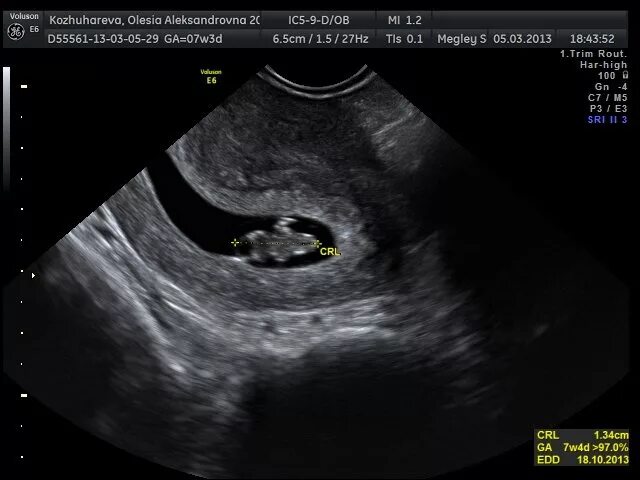

3 нед 4 дня